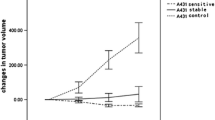

To determine the radiosensitivity of human HNX-OE xenografts, tumors were locally irradiated with escalating doses of external beam radiation. Tumor growth in all treatment groups was inhibited compared with that in the control mice, in a dose-dependent way (Fig. 1). Tumor regrowth started 9 and 23 days after start of treatment in the groups treated with 10 and 14 Gy and 18 and 22 Gy, respectively. A summary of treatment effects is listed in Table 2. All treated groups showed an ILS, and MTD was found to be 22 Gy. Statistical analysis demonstrated a significant difference (P < 0.001) between treated and control tumors. In addition, a significant difference was found between the 10 and 14 Gy group and the 18 and 22 Gy groups (P < 0.007).

No significant difference was found between tumors treated with doses of 18 and 22 Gy (P = 0.379).